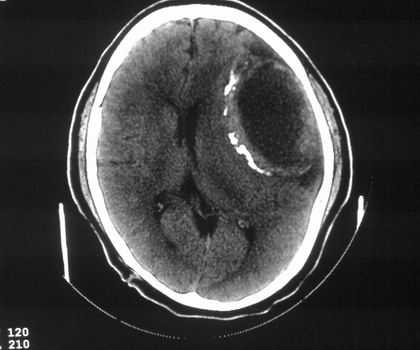

以下是引用影像孺子牛在2008-4-29 21:20:00的发言:[br]首先病变定位在脑外,根据ct密度及mri信号特征考虑慢性硬膜下血肿不连续环形钙化。

以下是引用周战梅在2008-4-29 23:12:00的发言:[br]脑外病变,蛛网膜下腔增宽,囊壁点状、环形钙化,增强扫描呈不均匀环状强化,考虑为囊性脑膜瘤可能性大,慢性脓肿、血肿机化、胆脂瘤不能除外。